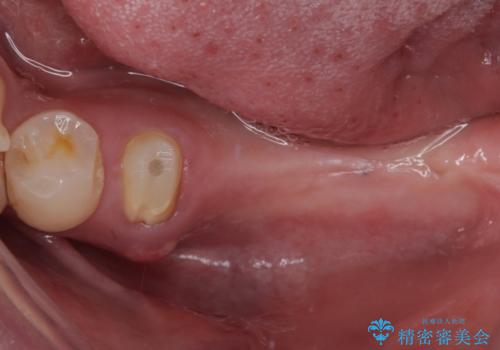

- むし歯を放置したままで、インプラント治療を希望して来院された患者様です。

左右ともにインプラントが必要な状態でした。

左下小臼歯は根管治療で対応する予定でしたが、診断のために歯肉を開いたところ頬側に垂直破折が認められたため、抜歯即時埋入インプラントによる補綴治療を選択することとしました。

右下は大臼歯部の歯は抜歯即時埋入インプラントにて、手前の歯は保存して補綴治療を行うこととしました。